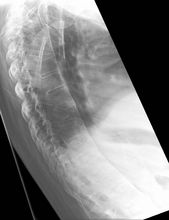

The earliest changes demonstrable by plain x–ray shows erosions and sclerosis in sacroiliac joints. Progression of the erosions leads to widening of the joint space and bony sclerosis. X-ray spine can reveal squaring of vertebrae with bony spur formation called syndesmophyte. This causes the bamboo spine appearance. A drawback of X-ray diagnosis is the signs and symptoms of AS have usually been established as long as 7–10 years prior to X-ray-evident changes occurring on a plain film X-ray, which means a delay of as long as 10 years before adequate therapies can be introduced.[19]

Osteoporosis is common in ankylosing spondylitis, both from chronic systemic inflammation and decreased mobility resulting from AS. Over a long-term period, osteopenia or osteoporosis of the AP spine may occur, causing eventual compression fractures and a back "hump".[37] Hyperkyphosis from ankylosing spondylitis can also lead to impairment in mobility and balance, as well as impaired peripheral vision, which increases the risk of falls which can cause fracture of already-fragile vertebrae.[37] Typical signs of progressed AS are the visible formation of syndesmophytes on X-rays and abnormal bone outgrowths similar to osteophytes affecting the spine. In compression fractures of the vertebrae, paresthesia is a complication due to the inflammation of the tissue surrounding nerves.